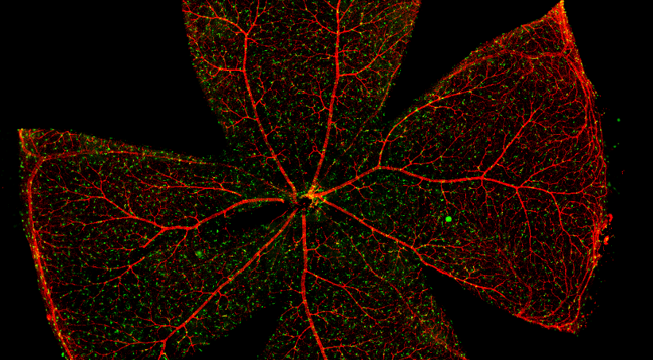

一般而言,眼底图像通常都是通过激光扫描成像进行采集,但是由于眼底可观测的视野往往是很有限的,一个患者的眼底信息需要多张扫描图像才能完全显示出来。这种局限性大大不利于病情进行全面的、细致的诊断。Tissue Cytometry全景组织流式定量分析技术进行全景图像获取,在单细胞、组织结构、细胞空间信息等多个层面进行定位、定性、定量分析。从而更好的对病变区域进行有针对性的跟踪观察和全面分析。

视网膜荧光样本中小胶质细胞胞体、神经纤维识别、血管识别、血管斑点识别、神经元与血管的距离分析。

1. 利用TissueFAXS系统进行玻片荧光的全景扫描。

5. 识别血管的Texa Red染色区域面积及强度。

血管识别:根据Texa Red通道进行识别,并去除面积小的及非同一焦面的血管,仅对确定的清晰的同一焦面的大血管进行面积统计。